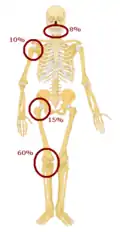

La tumeur se développe le plus souvent dans la région métaphysaire des os longs tubulaires, avec 42 % se produisant dans le fémur, 19 % dans le tibia et 10 % dans l'humérus. Environ 8 % des cas surviennent dans le crâne et la mâchoire, et 8 % dans le bassin[3].

Découverte par le chirurgien Alexis Boyer en 1806[5], cette tumeur touche particulièrement les os longs comme le fémur (40 %), le tibia (20 %), le pelvis (10 %), l'humérus (8 %), les os de la face (< 10 %) [6].

La tumeur peut être localisée à l'extrémité de l'os long. Le plus souvent, elle affecte l'extrémité proximale du tibia ou de l'humérus, ou l'extrémité distale du fémur. L'ostéosarcome tend à affecter les régions autour du genou dans 60 % des cas, dans 15 % des cas c'est autour de la hanche, 10 % à l'épaule et 8 % dans la mâchoire.